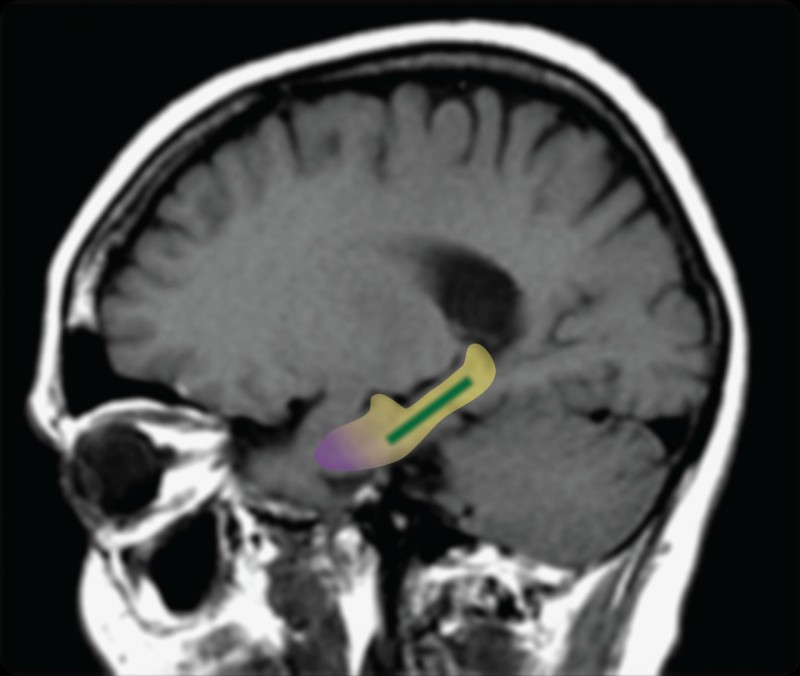

可可豆里提取的可可黄烷醇可以改善老鼠齿状回的神经连接

之前的研究工作,包括研究高级作者斯考特•斯摩尔(Scott A. Small)在他实验室进行的研究,都显示大脑特定部分齿状回的改变与衰老相关的记忆衰退有关。然而,在此之前研究结果只显示两者存在相关性,而没有发现存在因果关系的证据。为了查明齿状回是否是人类与衰老相关的记忆衰退的来源,斯摩尔和他的同事测试了一种名为可可黄烷醇的化合物是否会改善这一大脑区域的功能并改善记忆。之前研究发现从可可豆里提取的可可黄烷醇可以改善老鼠齿状回的神经连接。

在这项研究里,年龄为50至69岁之间的37名健康志愿者被随机分配接受高黄烷醇膳食(每日900毫克黄烷醇)或者低黄烷醇膳食(每日10毫克黄烷醇),连续进行三个月。在研究前后分别对被试者进行了大脑成像和记忆测试。大脑成像测量了齿状回的血容量,而记忆测试则涉及20分钟的识别图案训练,用于评估齿状回控制的一种记忆类型。

“当我们对研究被试者的大脑进行成像,我们发现那些服用高可可黄烷醇饮料的被试者的齿状回功能存在明显改善,”研究首席作者塔布研究所神经心理学助理教授亚当•布瑞克曼(Adam M. Brickman)博士这样说道。服用高可可黄烷醇饮料的被试者在记忆测试方面表现也更好。“如果一名被试者在研究开始时的记忆里相当于60岁老人,在经过3个月的膳食干预后,他的记忆力将变得类似于30岁或者40岁的中年人。” 斯摩尔博士说道。然而,他也警告称这项发现需要在更大人群中进行重复实验,这也是他的研究小组计划接下来进行的。